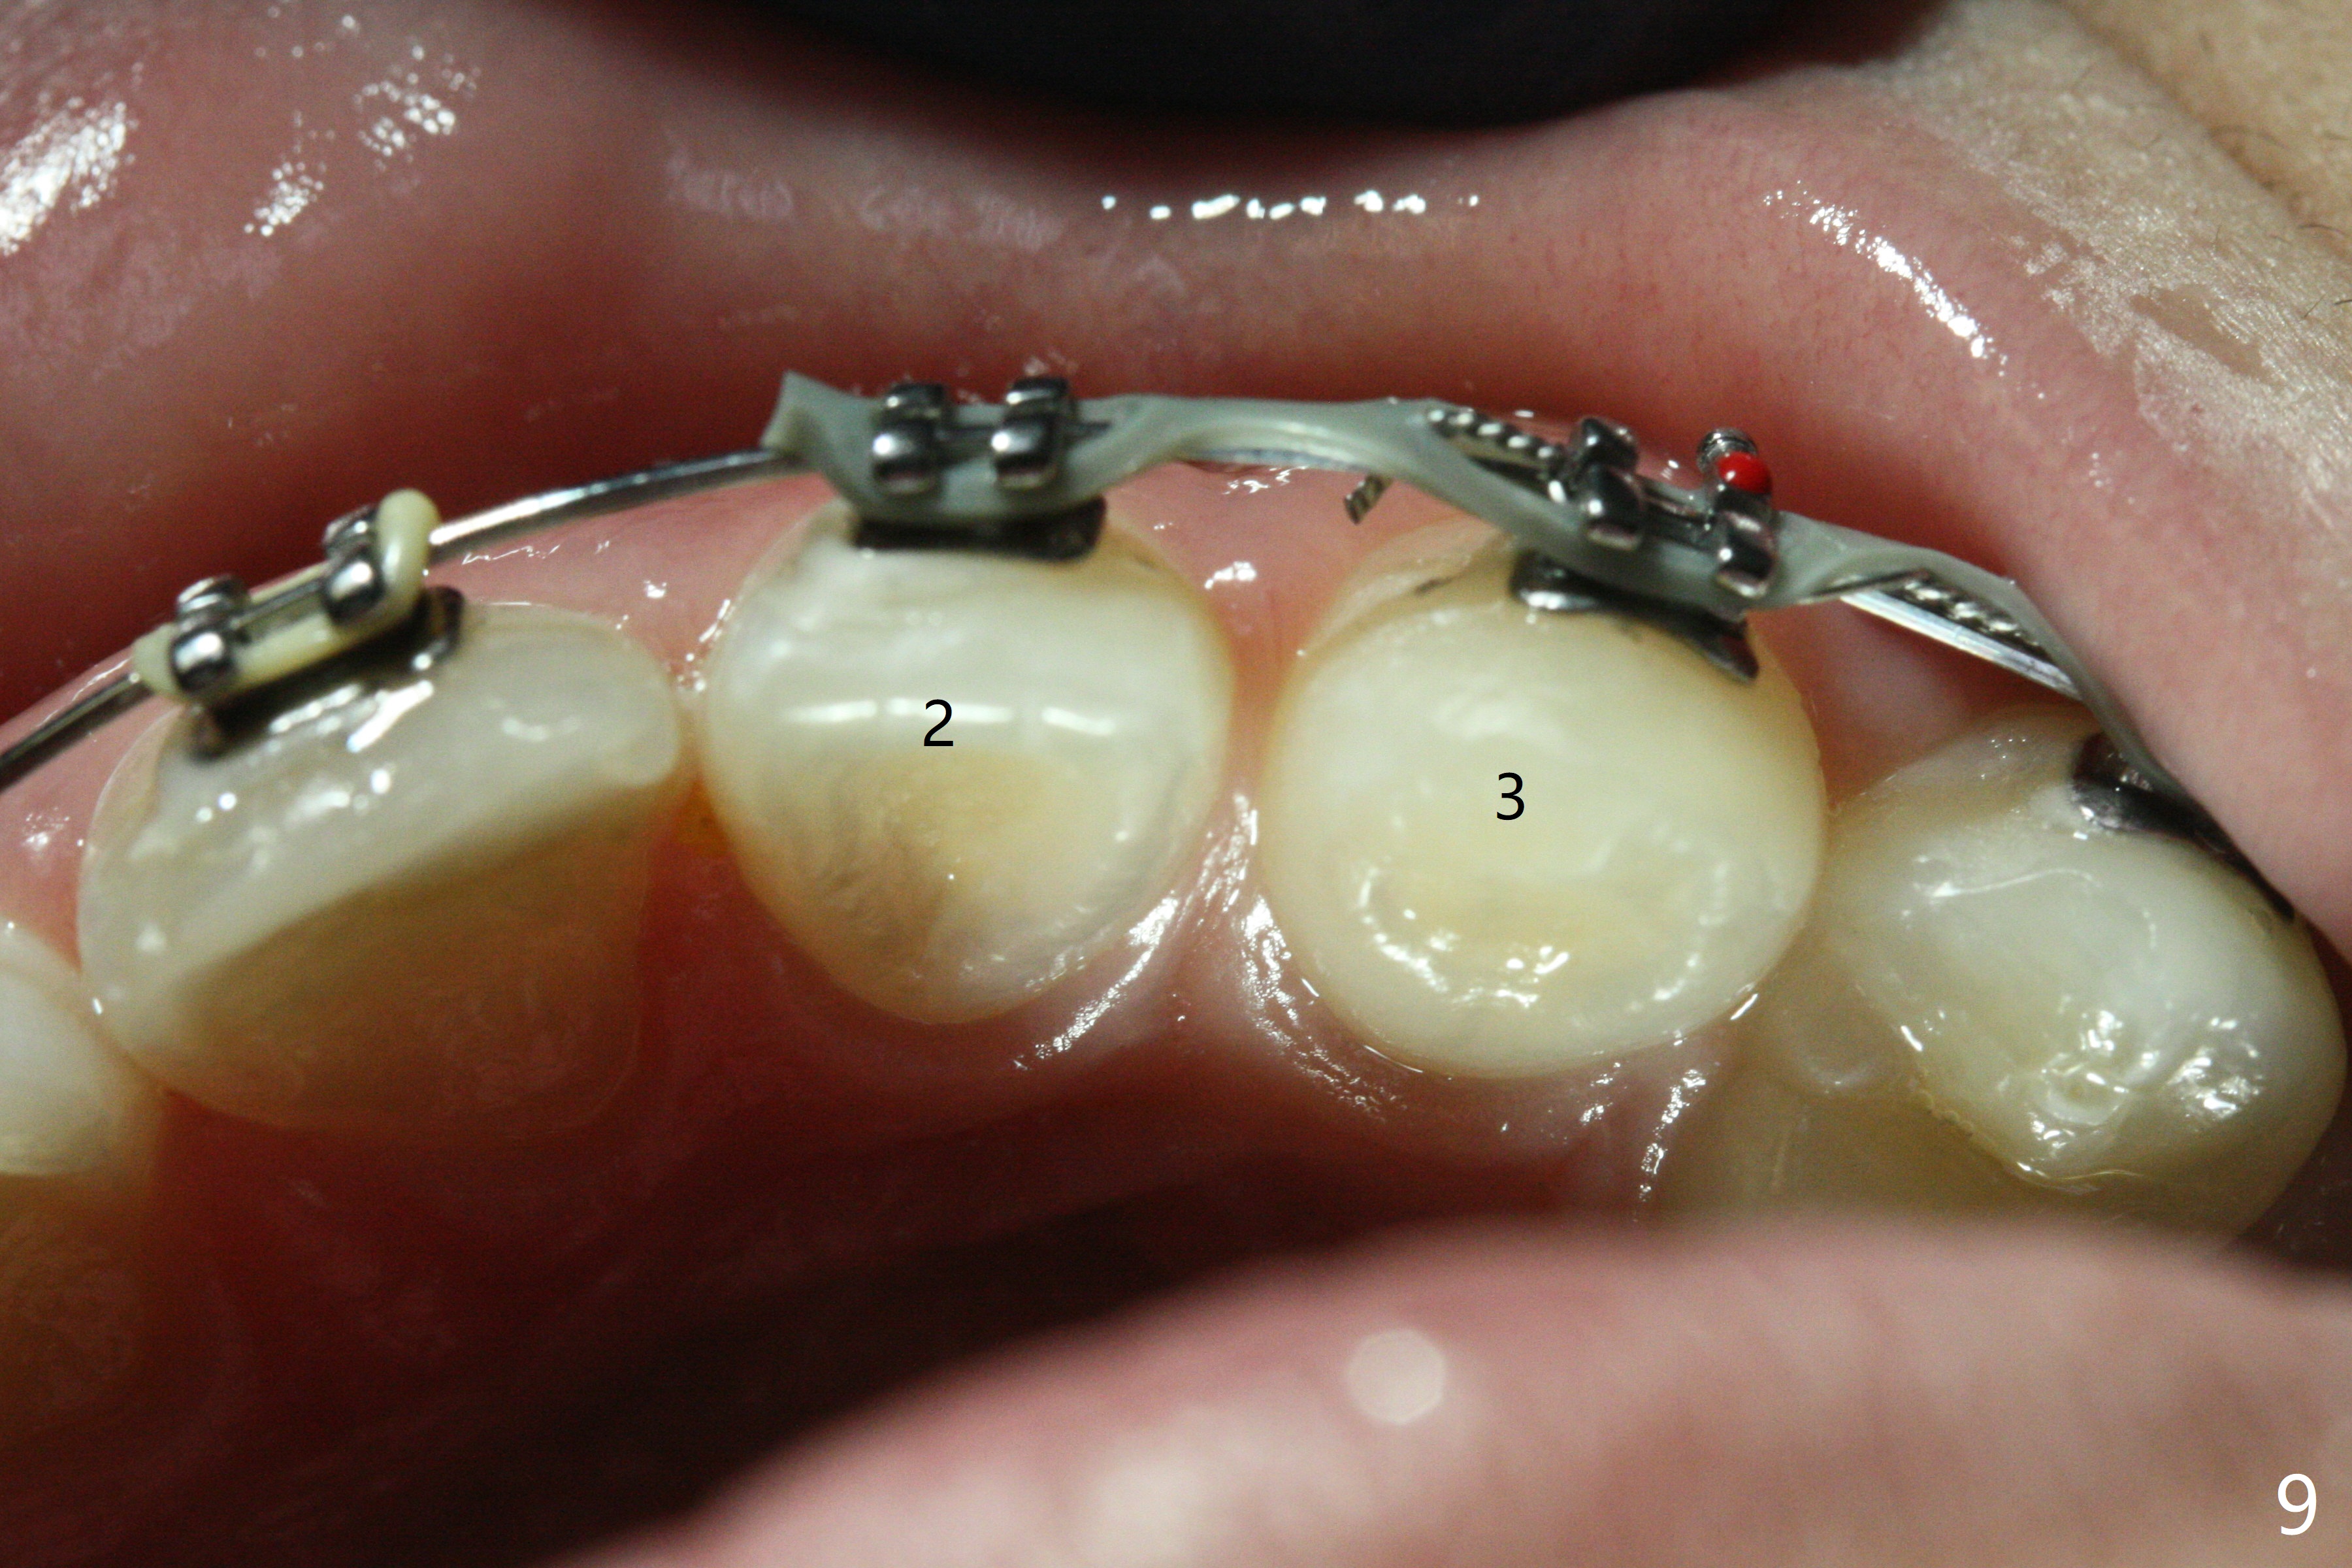

Nearly 6 months post banding (16x16 wires), LR5 has been overcorrected, while the upper dental midline appears to shift to the right (Fig.8). UL2 is going to be distalized (Fig.9). One months later, UL1 is to be distalized. Next appointment, check molar occlusion before any procedure. Panoramic X-ray taken 6 months post debanding shows no rotation at LR5 (Fig.10).